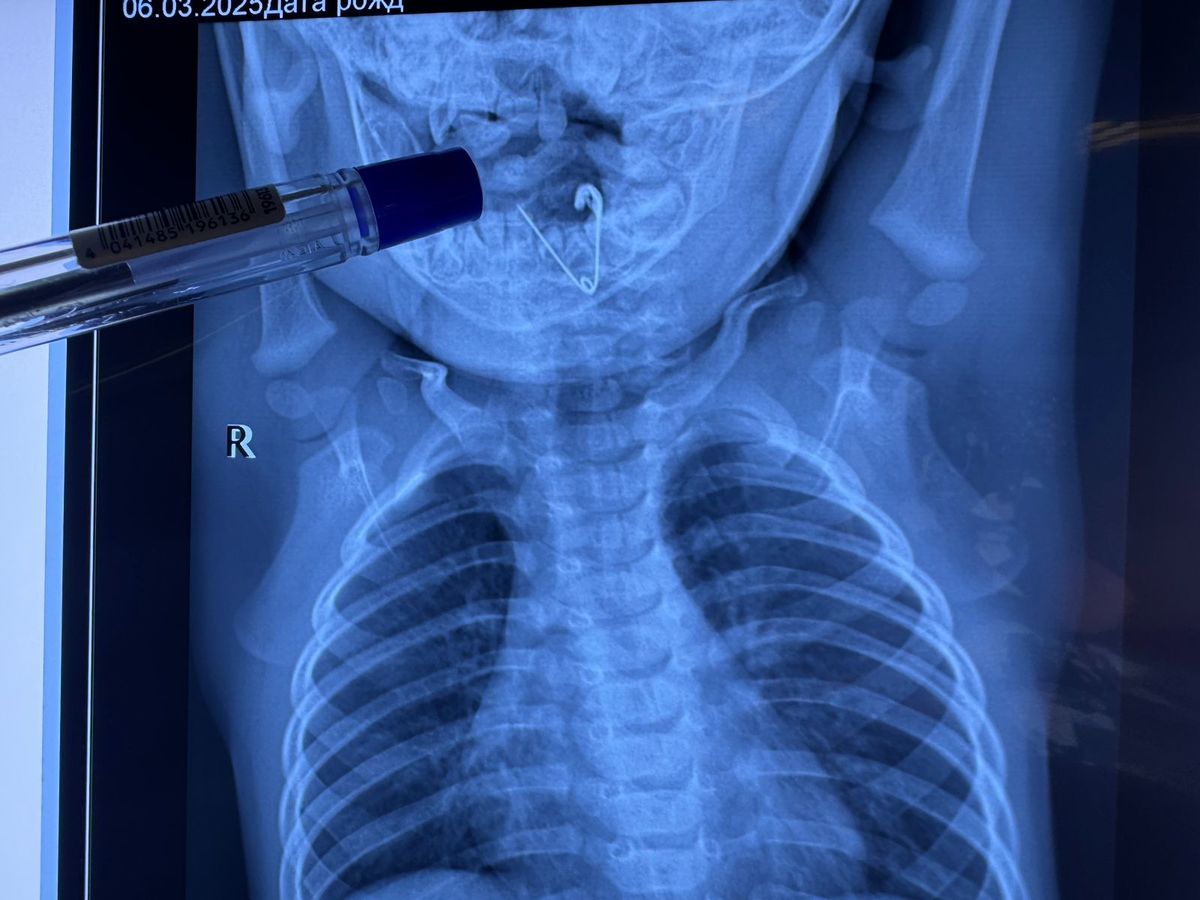

Бригада медиков госпитализировала маленького пациента в приёмное отделение Центральной районной больницы Черниговки. Здесь ему сделали обзорную рентгенографию органов грудной клетки. В пищеводе была обнаружена тень инородного тела.

Оперативно ребёнка доставили в Краевую детскую клиническую больницу № 1 Владивостока, где у врачей огромный опыт по извлечению самых сложных инородных предметов. Здесь малышу провели повторное рентгеновское исследование, подтвердившее диагноз. На снимке была чётко видна открытая булавка. Операцию по извлечению инородного тела провели заведующая лор-отделением первой детской больницы Светлана Таранова и её коллега – заведующий эндоскопическим отделением Алексей Ткачук. Врачи удалили предмет при помощи щипцов под контролем эндоскопической техники. Ребёнок перенёс операцию хорошо и вскоре будет выписан домой.